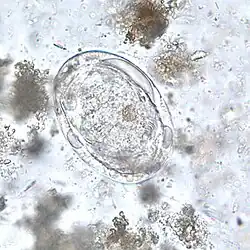

Schistosoma japonicum é um verme achatado parasita, pertencente do filo Platyhelminthes, classe Trematoda. É um importante parasita e um dos principais agente causadores de esquistossomose. Este parasita tem um largo espectro de hospedeiros, infectado pelo menos 31 espécies de mamíferos selvagens, incluindo 9 carnívoros, 16 roedores, um primata, dois insectívoros e três artiodáctilos. Pode ser considerada uma zoonose.[1]

Ciclo de vida

Em resumo, os ovos do parasita são libertados nas fezes e se entram em contacto com água, eles dão origem a larvas de vida livre. A larva tem que infectar o caracol da espécie Oncomelaria hupensis num período de um ou dois dias. Dentro do caracol, a larva passa por reprodução assexuada, através de vários estágios. Depois deste período de reprodução, o caracol terá que infectar um hospedeiro vertebrado com as características mais apropriadas. Assim que a larva cercária penetra a pele do hospedeiro, ela perde a sua cauda e começa a migrar pelo sistema circulatório até às veias mesentéricas, lugar onde se reproduze e efectua a postura dos ovos. Cada par deposita entre 1500 e 3500 ovos por dia nos vasos da parede intestinal. os ovos infiltram-se através dos tecidos e acabam novamente nas fezes.